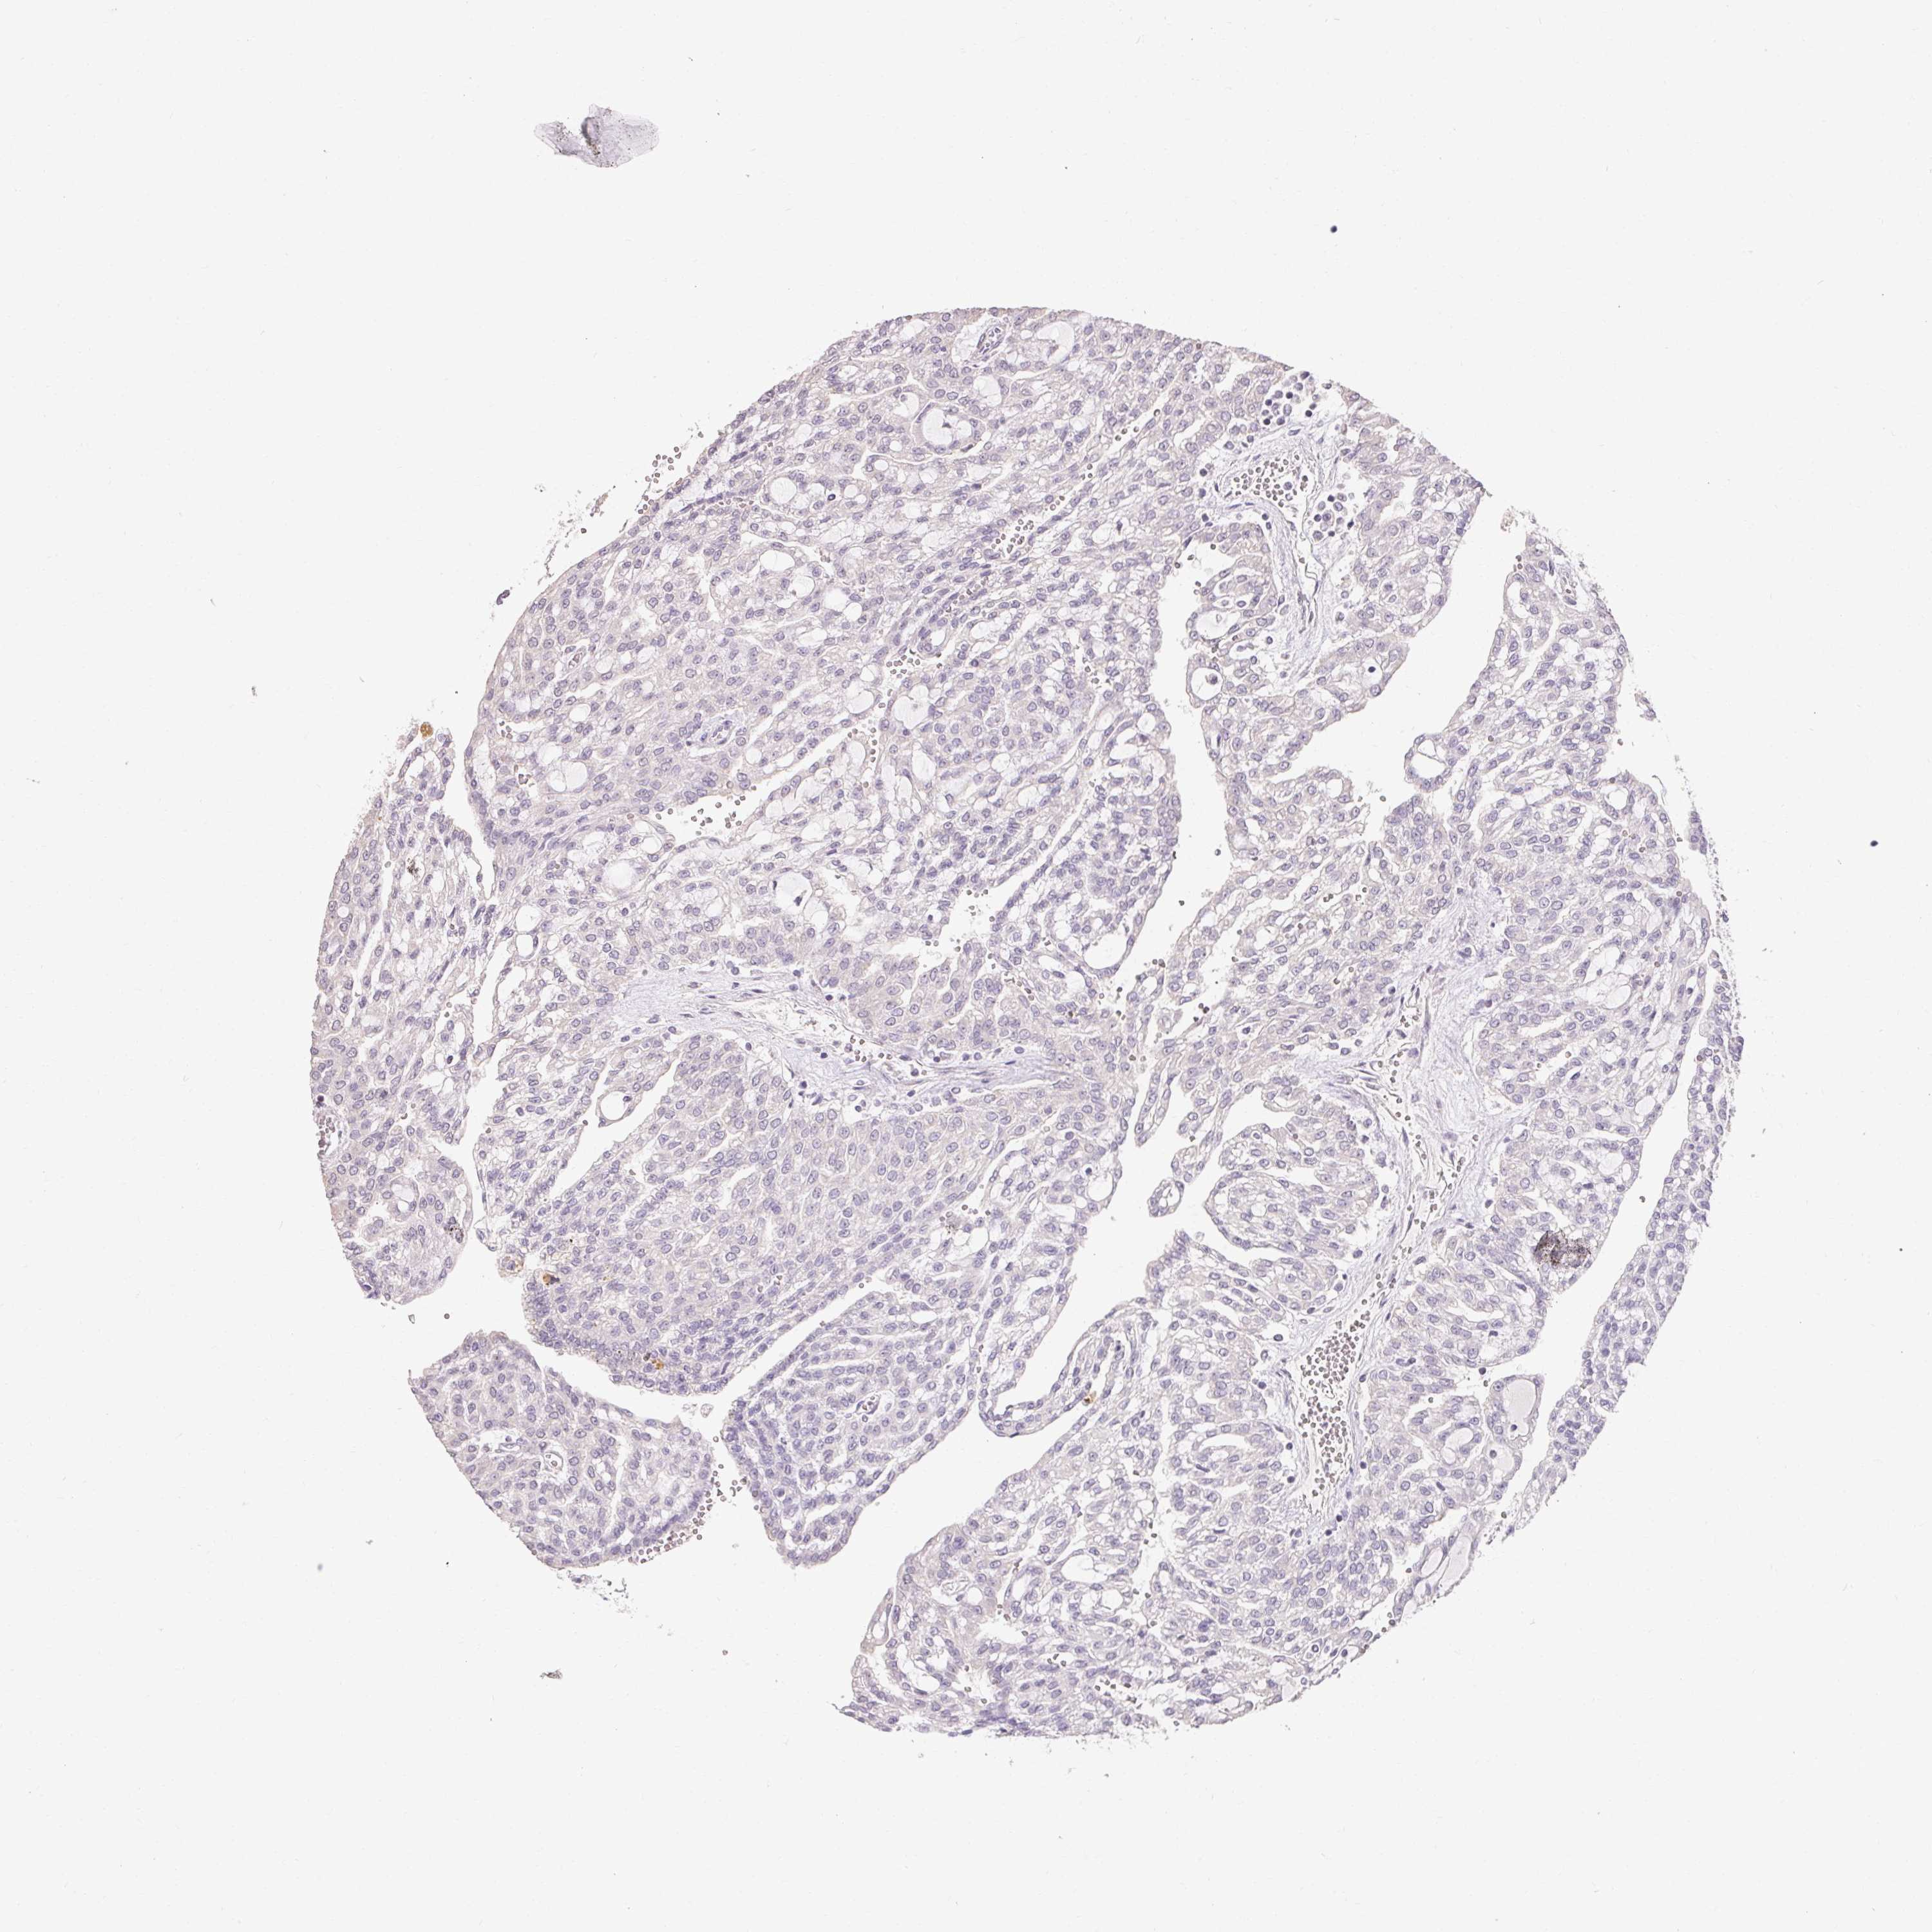

KIDNEY RENAL CLEAR CELL CARCINOMA (VALIDATION) - Interactive survival scatter ploti

The Survival Scatter plot shows the clinical status (i.e. dead or alive) for all individuals in the patient cohort, based on the same data that underlies the corresponding Kaplan-Meier plots. Patients that are alive at last time for follow-up are shown in blue and patients who have died during the study are shown in red.

The x-axis shows the expression levels (FPKM) of the investigated gene in the tumor tissue at the time of diagnosis. The y-axis shows the follow-up time after diagnosis (years). Both axes are complimented with kernel density curves demonstrating the data density over the axes. The top density plot shows the expression levels (FPKM) distribution among dead (red) and alive patients (blue). The right density plot shows the data density of the survived years of dead patients with high and low expression levels respectively, stratified using the cutoff indicated by the vertical dashed line through the Survival Scatter plot. This cutoff is automatically defined based on the FPKM cutoff that minimizes the p-score. The cutoff can be changed by dragging the vertical line or by entering a cutoff value in the square labeled "Current cut-off".

Under the Survival Scatter plot the p-score landscape (black curve; left axis) is shown together with dead median separation (red curve; right axis). Dead median separation is the difference in median mRNA expression between patients who have died with high and low expression, respectively. It is calculated as follows: median FPKM expression of dead patients with high expression - median FPKM expression of dead patients with low expression. This is intended to aid the user in visually exploring custom cutoffs and the associated p-scores and dead median separation.

Individual patient data is displayed and can be filtered by clicking on one or more of the category buttons on the top of the page. Categories describing expression level and patient information include: high, low, alive, dead, female, male and tumor stages. The scale of the x-axis can be toggled between linear and log-scale by clicking on the "x log" button. Mouse-over function shows TCGA ID, patient information and mRNA expression (FPKM) for each patient.

& Survival analysisi

Kaplan-Meier plots summarize results from analysis of correlation between mRNA expression level and patient survival. Patients were divided based on level of expression into one of the two groups "low" (under cut off) or "high" (over cut off). X-axis shows time for survival (years) and y-axis shows the probability of survival, where 1.0 corresponds to 100 percent.

MAP7D2 is not prognostic in Kidney Renal Clear Cell Carcinoma (validation)

: 2.62

P scorei

Log-rank P value for Kaplan-Meier plot showing results from analysis of correlation between mRNA expression level and patient survival.

N/A

Average pTPM 20.0

Number of samples 100